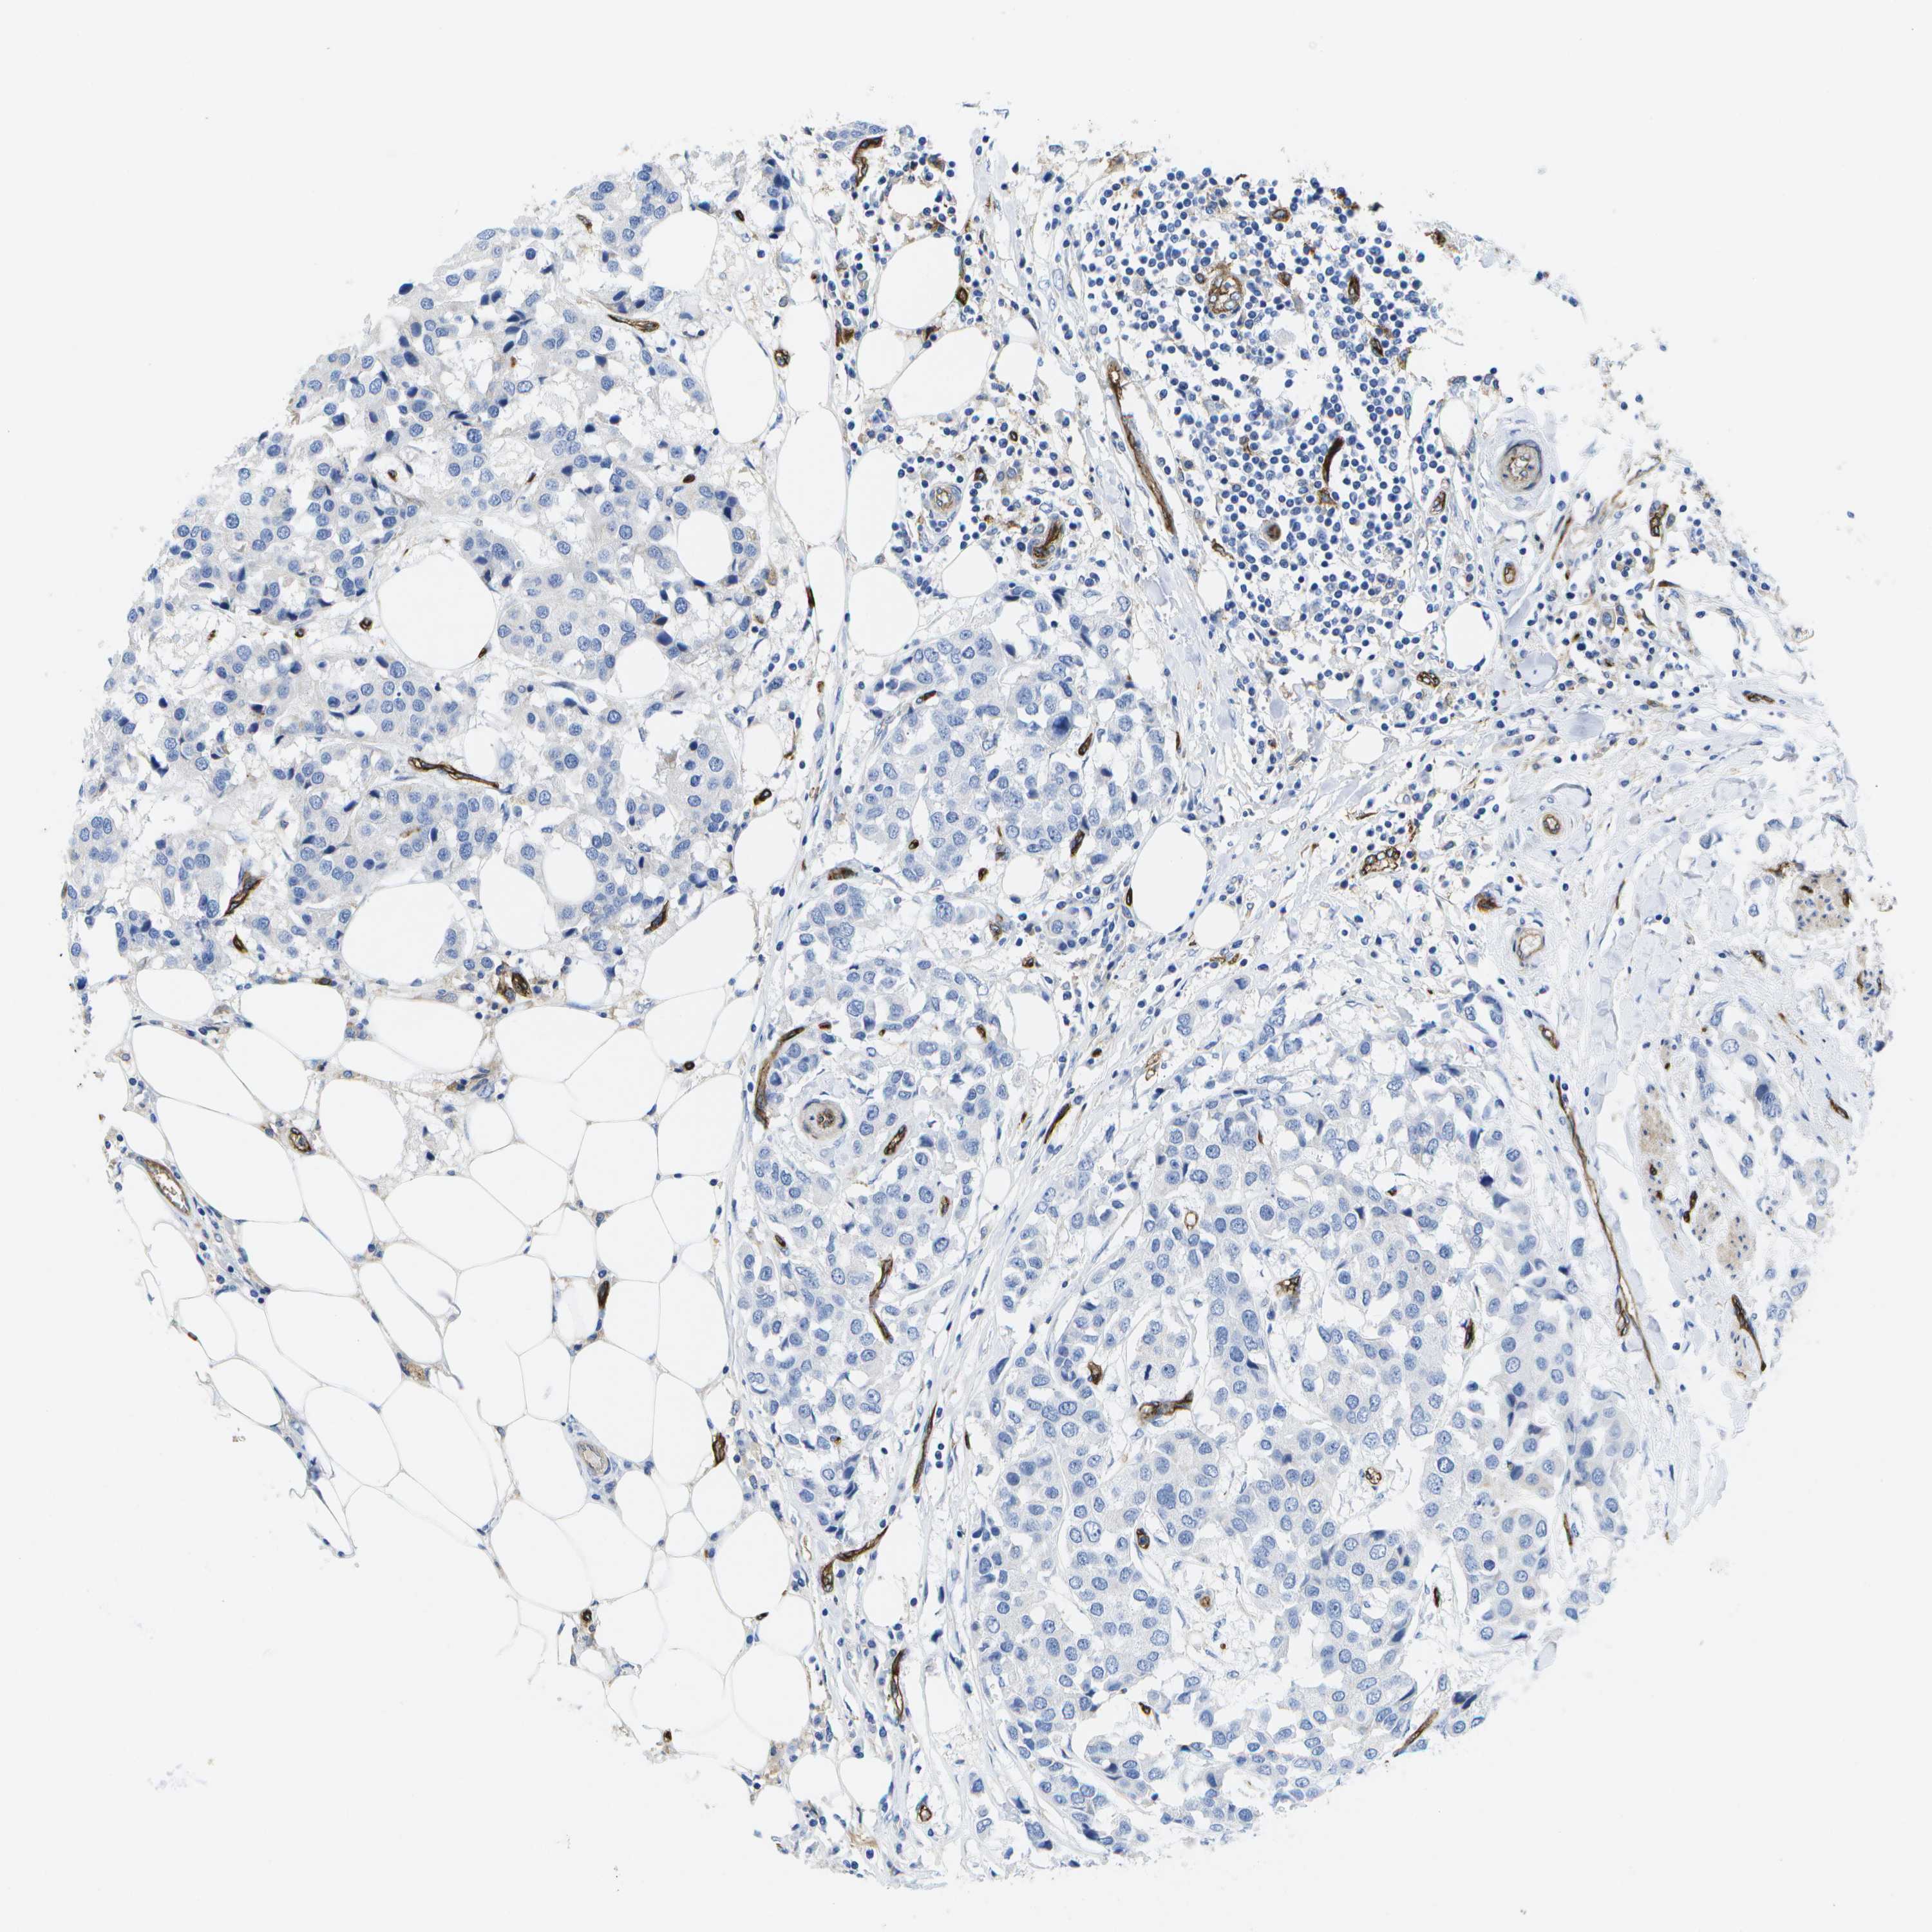

CANCER BREAST CANCER Show tissue menu

BRCA TCGA BRCA VALIDATION PROTEIN EXPRESSION